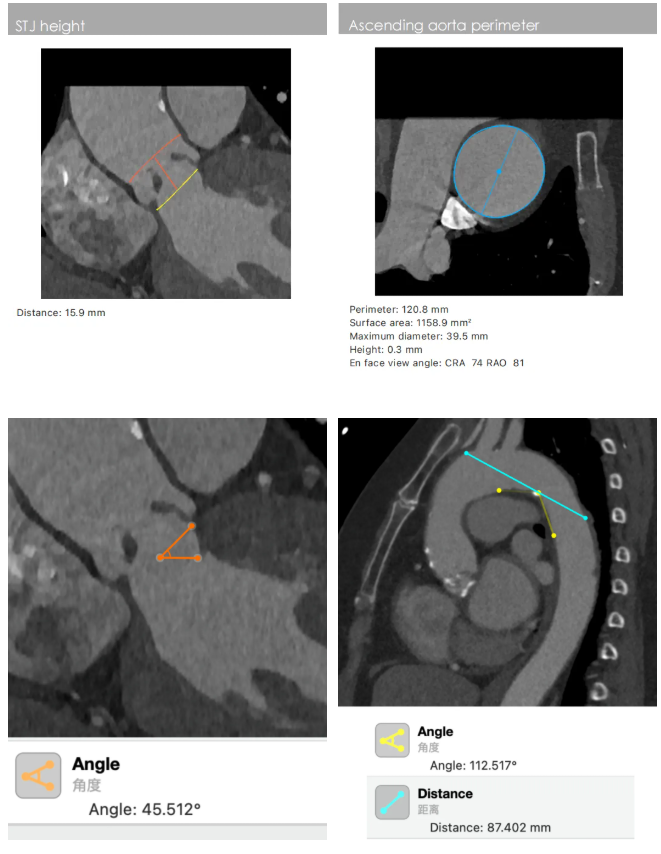

患者主动脉瓣重度狭窄并重度反流。CT显示三叶瓣,瓣叶增厚、中度钙化集中在瓣叶边缘与左无交界融合处,瓣环周长73.7 mm,均径23.4 mm,LVOT(左室流出道)周长73.9mm,STJ(窦管交界)周长91.5mm,升主动脉均径120.8 mm,瓣环角度可。左冠瓣叶长,LCA开口较低,有一定风险。